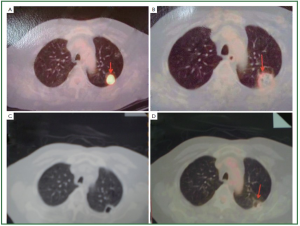

Niu and his colleagues (15) from Fuda Cancer Hospital, Guangzhou, reported the results of a total of 840 patients with non-small cell lung cancer who underwent percutaneous cryoablation in Fuda Cancer Hospital Guangzhou, China. Based on the TNM staging, there were 122 patients with stage IIa, 462 with IIb, 160 with IIIa, 64 with IIIb and 32 with IV. A total of 1,174 procedures of cryoablation were performed for 840 patients with lung cancer. There were 140 and 66 patients who underwent additional single and two sessions of cryoablation procedure, respectively, for recurrent tumors in the lungs. There were 62 patients who underwent additional session of cryoablation for liver metastases. After cryoablation, the size of the lesions increased initially, which was corresponding to the freezing margin exceeding 1 cm beyond the limit of the tumor. The cryotreated lesions then appeared shrinking or cavitated on CT images. During the follow-up, complete remission (CR) was observed in 86 patients (14.4%), partial remission (PR) in 588 patients (70.0%). However, the tumor recurred in 47.2% of the patients during a median follow-up of 34 months (range, 4 to 63 months), in the lungs, liver, brain, and bone. The recurrence at cryosite accounted 28.3% of cases. During the follow-up, the median survival of all patients was 23 months (range, 5-61 months) with 1-, 2-, 3-, 4-, and 5-year overall survival of 68%, 52%, 34%, 26% and 17%, respectively. Zhou et al. (35) in the same hospital observed therapeutic effects of cryosurgery combined iodine-125 seeds implantation in 140 patients with advanced lung cancer. However, the combination treatment did not show much better result than the whole group above mentioned. After 6 postoperative months the patients had CR of 16.8%, PR of 70.1%, stable disease (SD) of 7.4%, and progressive disease (PD) of 5.7%. The half-year and one-year survival rates were 94.3% and 65.7% respectively. Figure 2, 3 showed two patients with complete response as proven by histology.

Figure 2. The CT scan of one patient with lung cancer. A. Cancer prior to cryoablation; B. Percutaneous cryoablation under CT guidance; C. CT image 8 months after cryoablation; D. PET/CT image showed the lesion no activity 12 months after cryoablation.

Figure 3. PET/CT scan of one patient with small lung cancer. A. Cancer prior to cryoablation; B. PET/CT image 12 months after cryoablation; C. CT image showed the cavitated lesion 5 years after cryoablation; D. PET/CT image showed the lesion no activity 5 years after cryoablation.